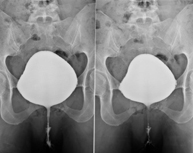

La urografia intravenosa (UIV) consisteix en l'obtenció d'imatges radiològiques seriades del ronyó, vies urinàries i bufeta. Aquest estudi requereix sempre l'ús d'un contrast iodat. - Cistografía (CUMS)

La cistouerotrografia miccional seriada consisteix en l'obtenció d'imatges radiològiques per valorar l'anatomia i la funció de la uretra i la bufeta amb l'administració de contrast iodat a través d'una sonda vesical. - Uretrocistografia (Uretro-Cums)

La uretrocistrografia retrògrada i miccional consisteix en l'obtenció d'imatges radiològiques per valorar l'anatomia i la funció de la bufeta i de la uretra. S'aplica material de contrast a través d'una petita sonda que es troba a la uretra i s'obtenen imatges durant l'ompliment i el buidatge de la bufeta. - Pielografia ascendent per catèter

Estudi que utilitza els raigs X per obtenir una imatge dels ossos de maluc i descartar luxacions. - Cistografia

La cistouretrografia miccional seriada consisteix en l'obtenció d'imatges radiològiques per valorar l'anatomia i la funció de la uretra i la bufeta amb l'administració de contrast iodat a través d'una sonda vesical.